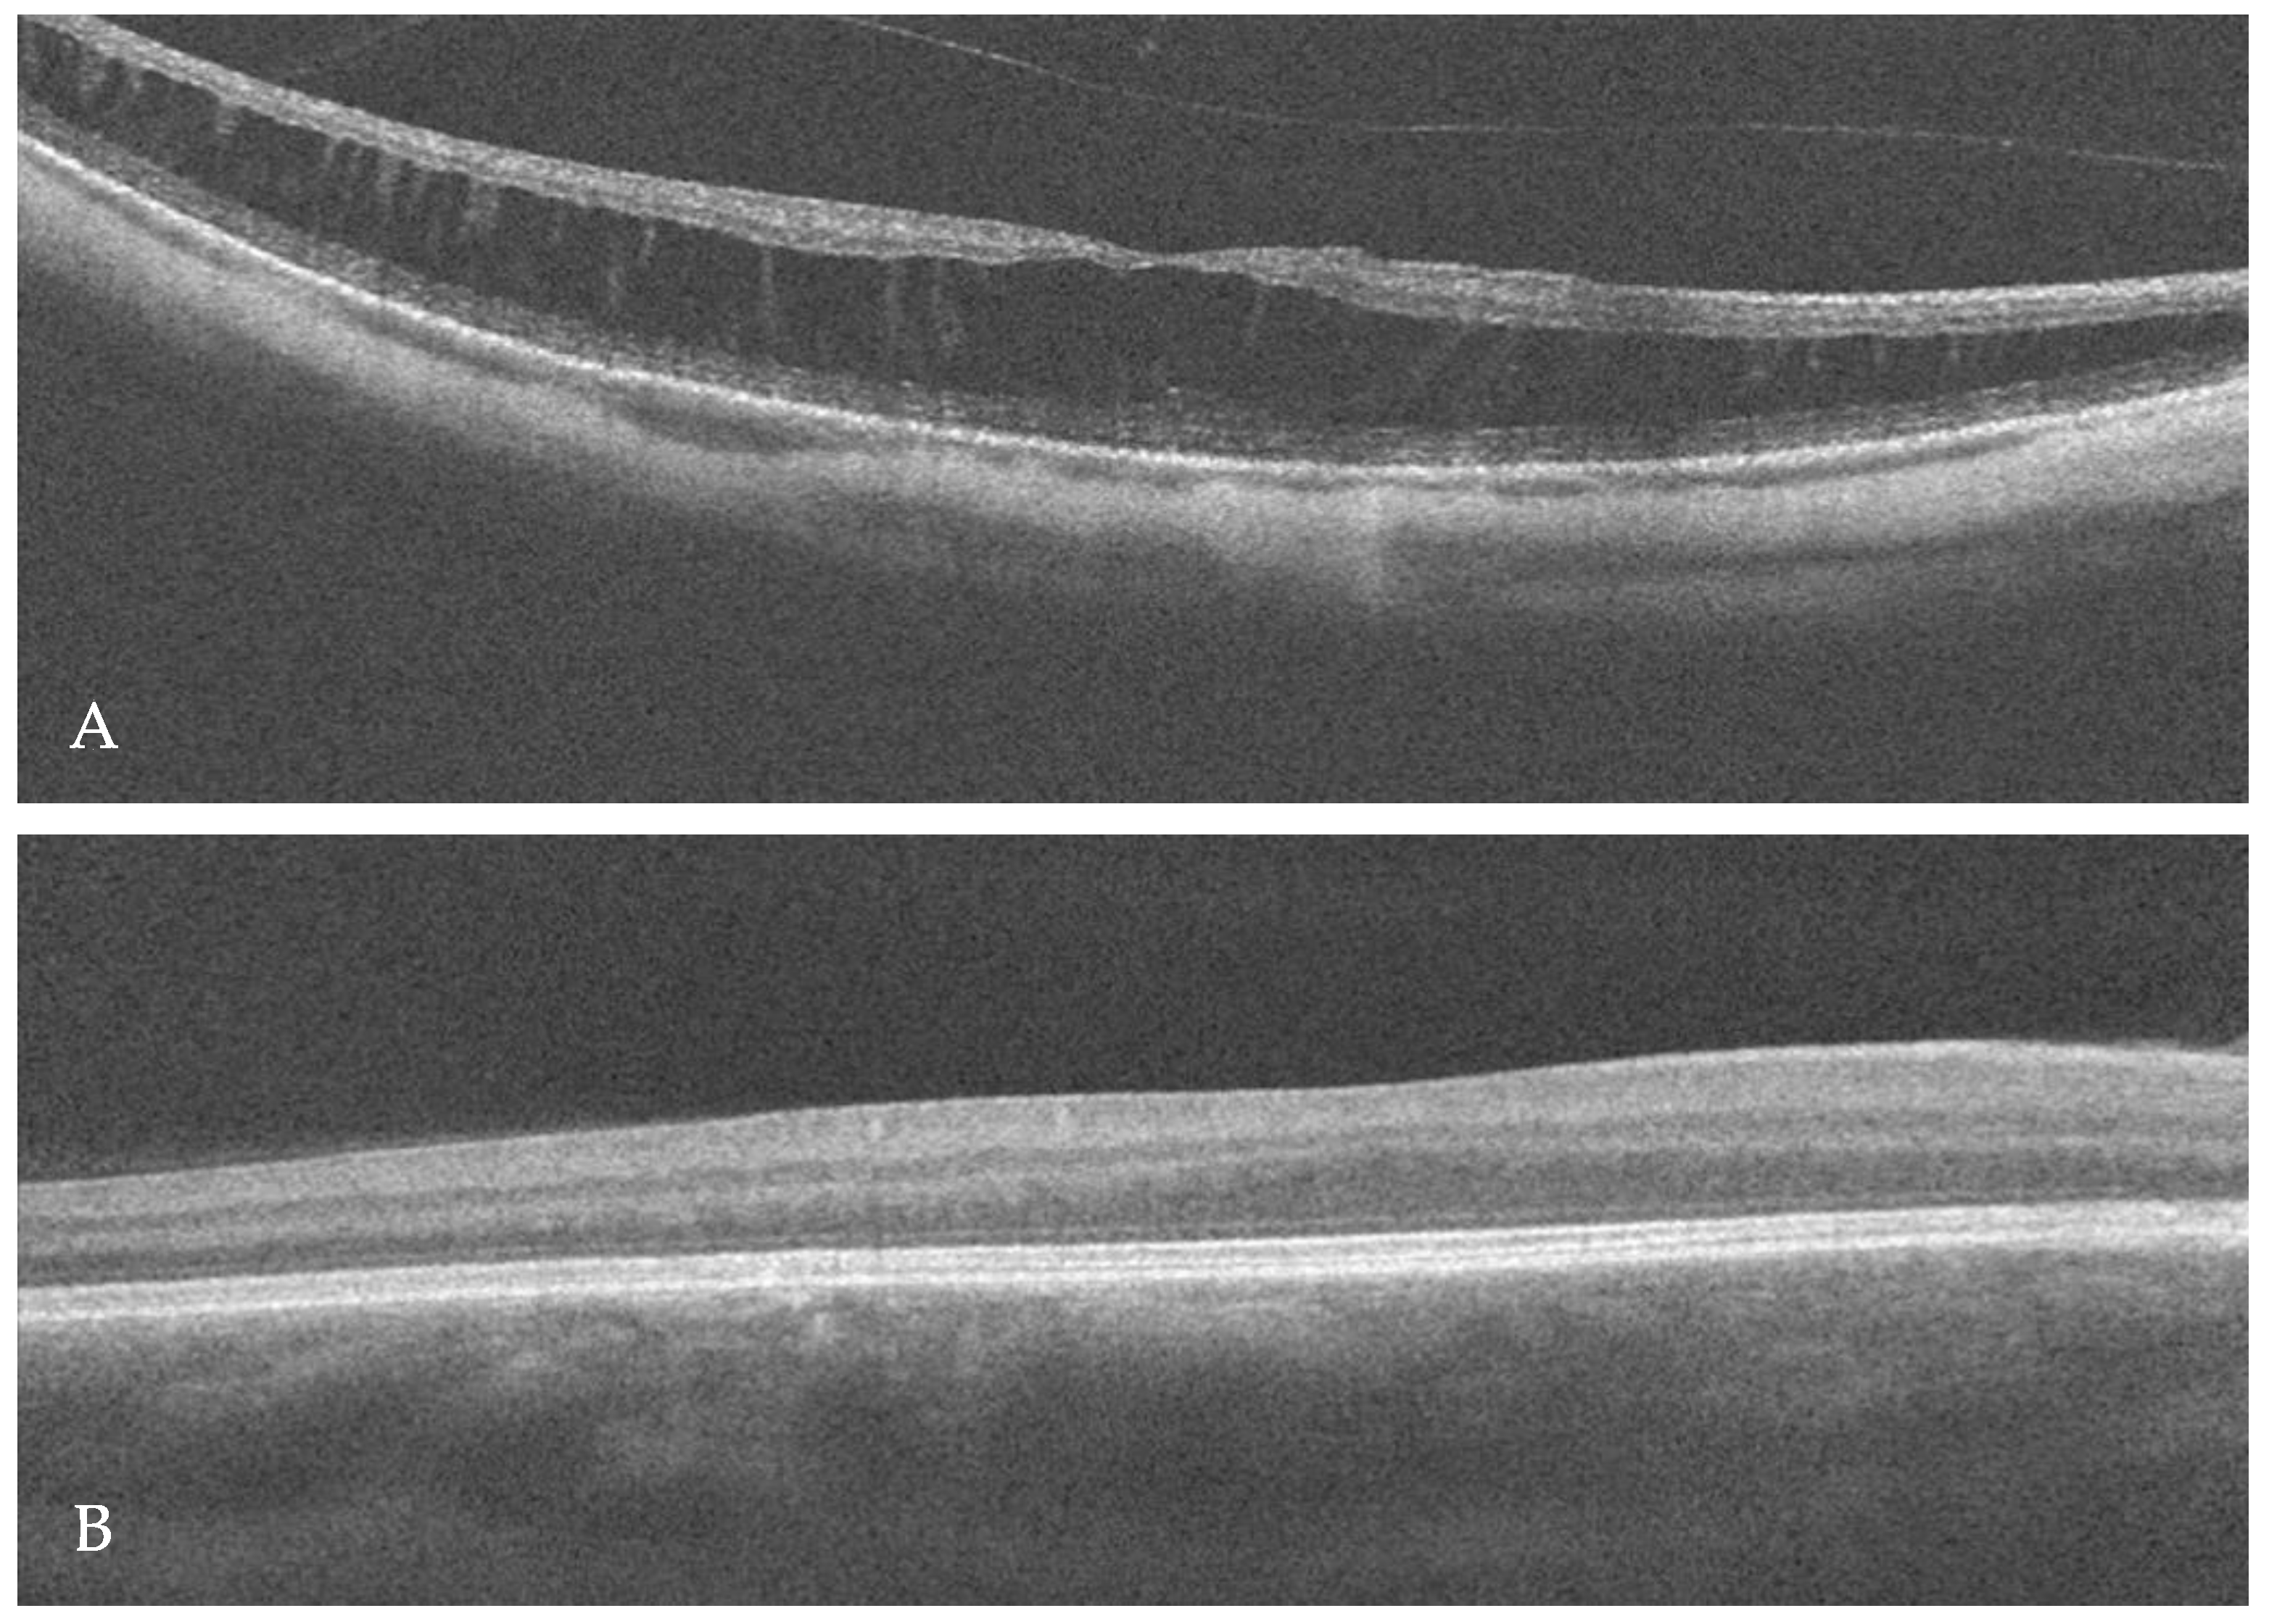

2. Case Report